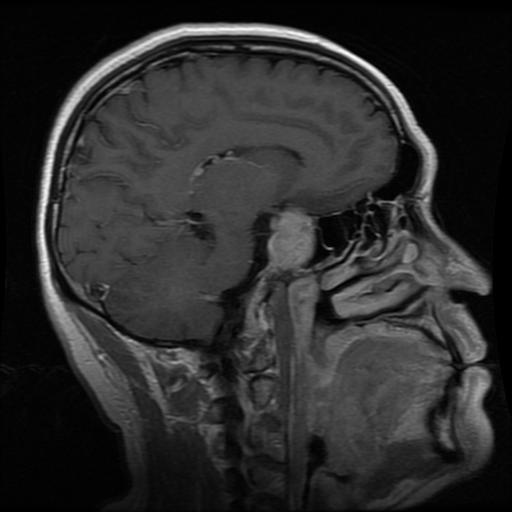

Glioma: Gliomas are irregularly shaped and often infiltrate surrounding tissues, presenting significant challenges for precise boundary definition. These complexities require robust segmentation techniques to capture their variable morphology. As shown in Figure 1, gliomas exhibit irregular and diffuse growth patterns, which are highlighted through annotated tumor masks.

The original collection contains 7,023 brain MR images across four classes: glioma, meningioma, pituitary tumour, and non-tumorous (the latter sourced from Br35H). We then applied the following steps to ensure consistency and quality: Original Image Binary Mask Tumor Region Overlay Axial

Figure 1: Samples of Glioma segmentation across different imaging planes

The dataset encompasses four distinct classes: ”Glioma”, ”Meningioma”, ”Pituitary” tumors, and ”non-tumorous”. As detailed in Section Overview of Brain Tumors, each class presents unique characteristics and complexities. This subsection offers representative visual examples from each class, including raw MRI scans alongside their annotated tumor masks, emphasizing the diversity and precision of the dataset. Glioma: Gliomas are irregularly shaped and often infiltrate surrounding tissues, presenting significant challenges for precise boundary definition. These complexities require robust segmentation techniques to capture their variable morphology. As shown in Figure 1, gliomas exhibit irregular and diffuse growth patterns, which are highlighted through annotated tumor masks. Meningioma: Meningiomas arise from the meninges and are generally well‑circumscribed and homogeneous, making them easier to segment. However, their location adjacent to critical structures such as dural sinuses and cranial nerves can complicate diagnostic tasks. An example of a meningioma and its segmentation mask is presented in Figure 2, illustrating the clarity of its boundaries. Pituitary Tumors: Located at the base of the brain near critical structures like the optic chiasm, pituitary tumors demand careful delineation to avoid diagnostic errors. As shown in Figure 3, the segmentation accurately captures the tumor’s boundaries without encroaching on adjacent critical regions. Non-tumorous: This control class includes both healthy brain scans without visible abnormalities and scans with non-neoplastic, space-occupying lesions (e.g., cysts, abscesses, or vascular malformations). Incorporating such cases improves the dataset’s robustness for both binary (tumorous vs. non-tumorous) and multi-class classification tasks. Figure 4 presents representative examples of healthy and non-tumorous lesion cases across different imaging planes.Tumor Mask and Annotation Quality